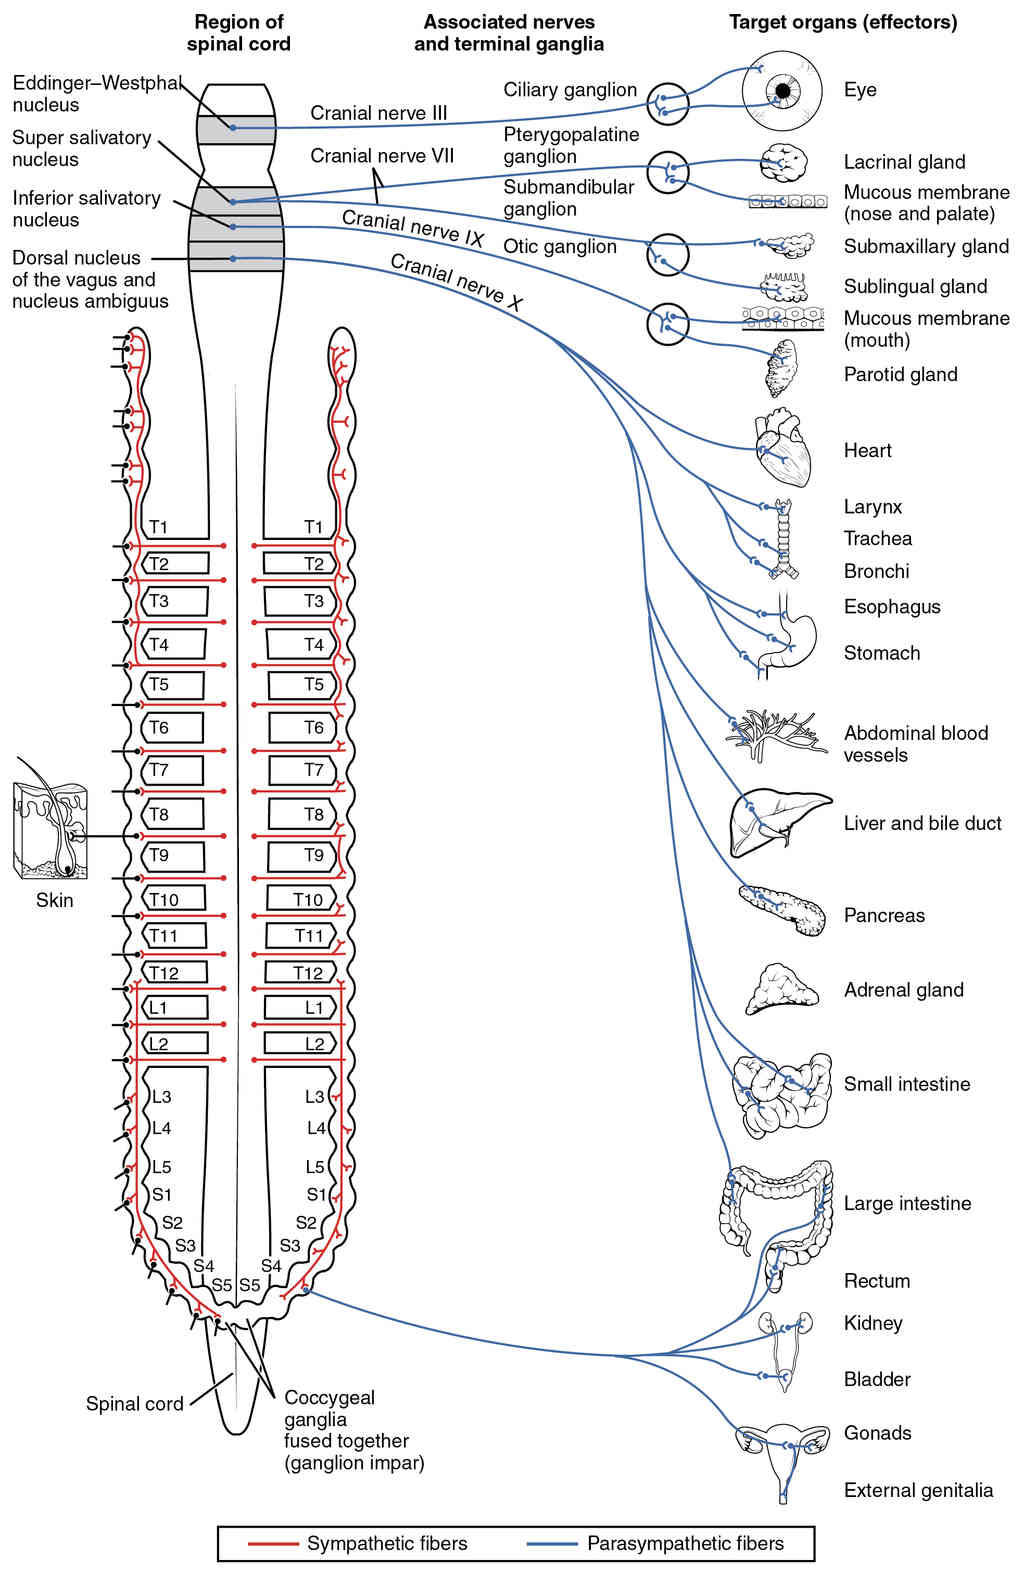

This page is under construction. For now, it is just a resource of the images found in the OpenStax Anatomy and Physiology Handbook. It wil slowly change into a revision tool. Each slide has a number. Use this to refer to the slide. When completed, it will have an unlabelled section, with labelled slides in parallel. On the unlabelled slides, write your answer and use the labelled slide to assess yourself. Keep track by also noting the number on each slide. Improvement at each attempt is important, more so than full marks on a first attempt.